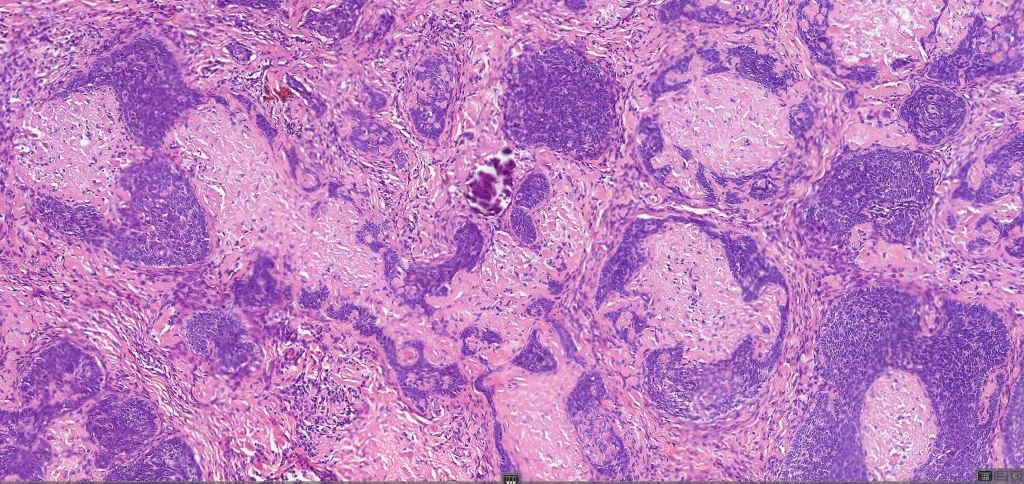

•Sharply circumscribed, unencapsulated nodule in deep dermis +/- subcutaneous fat or deeper (trichoepithelioma is much more superficial)

•Variably sized but generally large, basophilic tumor nodules composed of small uniform basaloid cells with minimal cytoplasm

•Variable keratocysts

•A rich fibromyxoid mesenchymal stroma with variable papillary mesenchymal bodies (sometimes these are absent)